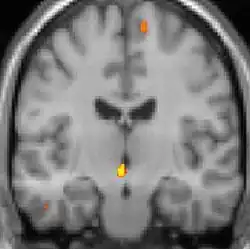

| Voxel-based morphometry shows brain area structural differences. | ||

Positron emission tomography (PET) scans indicate the brain areas which are activated during attack only, compared to pain free periods. These pictures show brain areas that are active during pain in yellow/orange color (called "pain matrix"). The area in the center (in all three views) is activated only during cluster headaches. The bottom row voxel-based morphometry shows structural brain differences between individuals with and without CH; only a portion of the hypothalamus is different.[36]